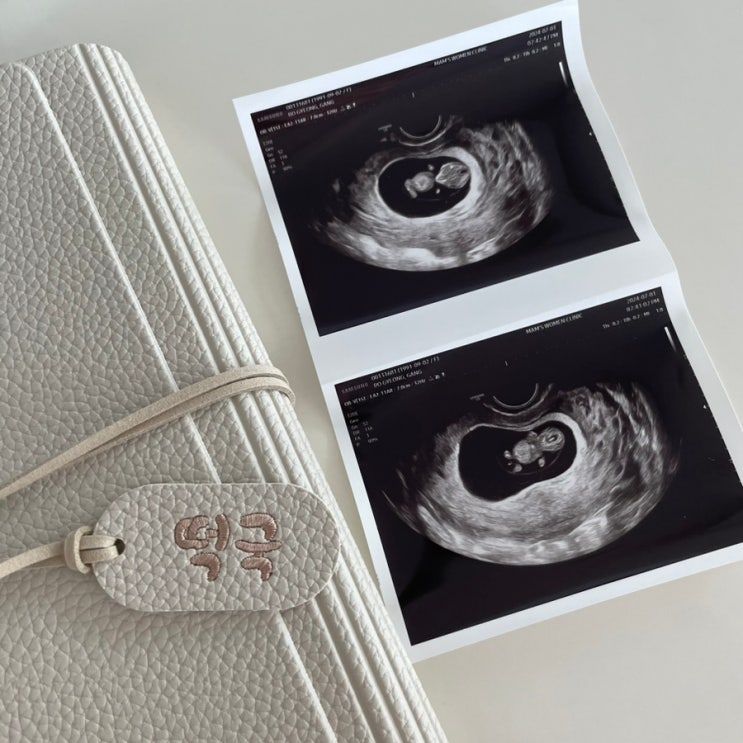

임신 7w5d / 태명 정하기 / 울산 맘스여성병원 / 울산북구보건소 임산부 등록

심장소리를 듣고 태명을 지어주기로 했다. 신랑이랑 엄청난 고민을 하고 결정한 태명은 ♥️떡국이♥️ 예...